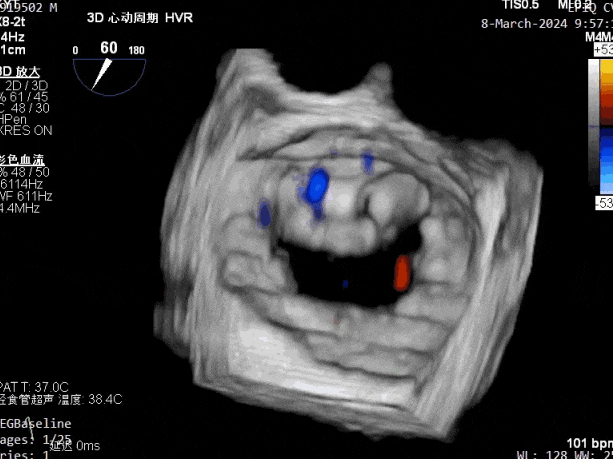

瓣膜夹释放前评估,二尖瓣反流减轻

瓣膜夹释放前评估,二尖瓣平均跨瓣压差及瓣口面积

释放瓣膜夹后评估,二尖瓣呈双孔,外侧仍有残余反流

第二个瓣膜夹释放前评估,二尖瓣反流减轻

第二个瓣膜夹释放前评估,二尖瓣平均跨瓣压差及瓣口面积

第二个瓣膜夹释放后评估,二尖瓣呈双孔,外侧仍有残余反流

第三个瓣膜夹释放前评估,组织桥张力稳定

第三个瓣膜夹释放前评估,二尖瓣平均跨瓣压差

第三个瓣膜夹释放后评估,释放后评估,二尖瓣呈双孔,组织桥张力合适,瓣膜夹轴向与二尖瓣闭合线垂直,无残余反流

肺静脉血流频谱恢复为收缩期正向